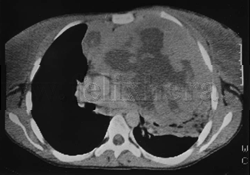

Linfoma de células B |

Bocio endotorácico |